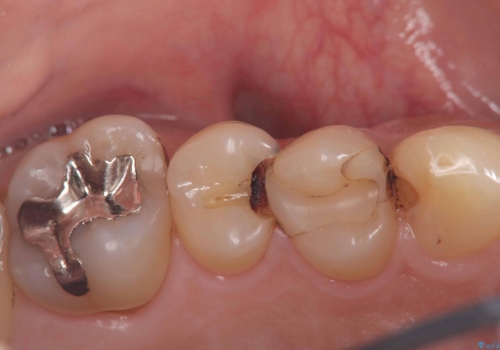

- 奥歯の被せ物が欠けたを主訴に来院された患者様です。欠けてしまった被せ物を除去後セラミックインレーで治療を行いました。

欠けた範囲が大きく被せ物を外して後、セラミックインレーで治療を行いました。欠けたままの状態を放置しているとそこに食べ物が詰まり虫歯になってしまうので早めの治療が必要です。